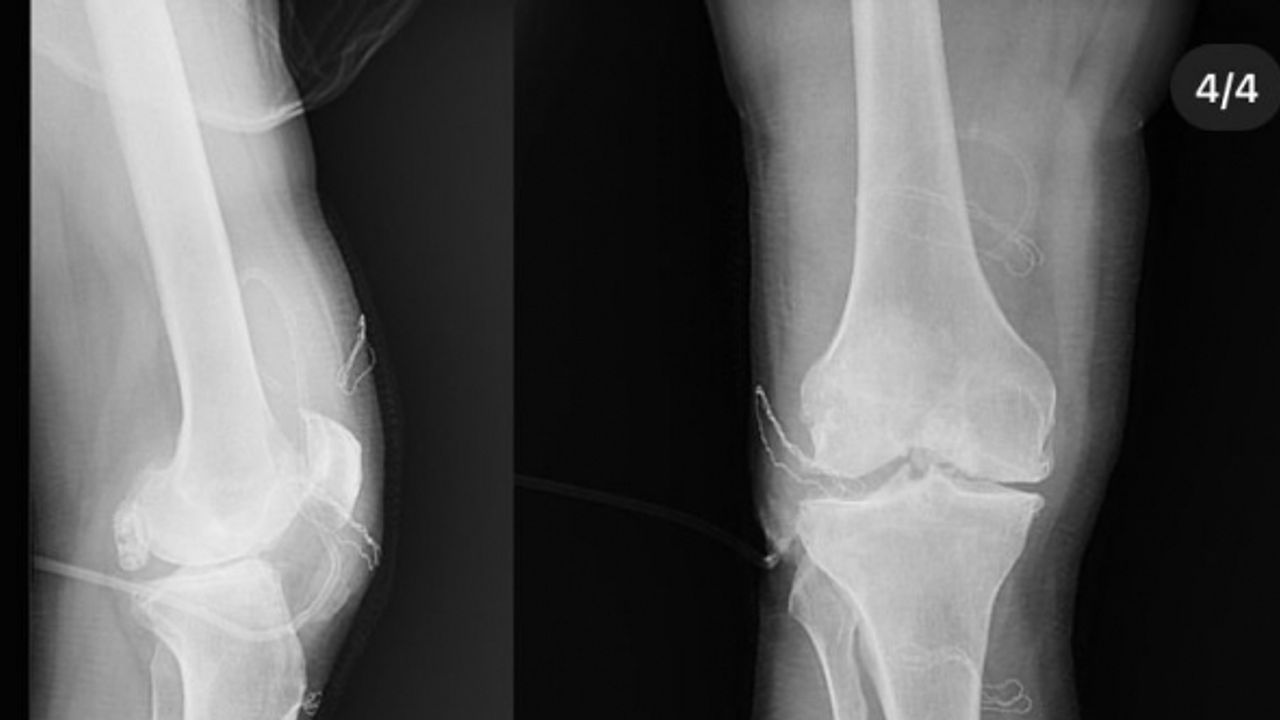

Diz ağrısı şikayeti ile geldiği Düzce Üniversitesi Tıp Fakültesi Hastanesi’nde ameliyata alınan hastanın dizlerinden toplam 41 adet multipl sinovial kondromatozisi çıkartıldı. Özellikle diz eklemi çevresinde görülmekle birlikte kalça, dirsek ve diğer eklemlerde de görülen, ufak parçalardan oluşan cisimler olarak tanımlanan eklem faresi, eklem çevresinde eklem sıvısı ya da sinoviyumda görülen kıkırdak ya da kemik parçalarıdır. Eklem farelerinin boyutları birkaç milimetreden birkaç santimetreye kadar çıkabiliyor.